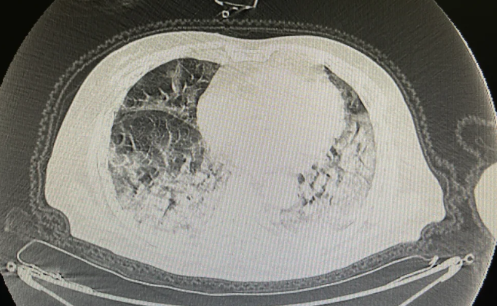

通常,白肺是可以得到医治的,死亡率限制在50%左右。白肺一般是指的重症肺炎其在X光检查下的表现,肺部显影呈一大片的白色状而得名。形成白肺一般都预示着肺部有被炎症所侵润。大部分肺部疾病可以并发白肺的现象,采用保护性肺机械通气等措施,改善患者氧气供应,有利于病情的改善。

感染新冠病毒的患者出现白肺,一般是因为患者的肺泡内存在大量渗出物,会出现实变和纤维化,在影像学上的病理表现为肺部的实变、肺部的磨玻璃影、肺部的单片影等。

如果病情进展较迅速,会出现双肺病变的迅速加重,甚至可以出现肺实变,称为白肺。如果出现白肺,说明肺泡内已经存在大量的渗出物,患者对氧气的氧合能力低,病情会非常危重,预后较差。

白肺是指在X线胸片检查或肺部CT检查中,肺间质组织出现大面积白色病变的表现

白肺的症状大多发生在重症肺炎中,因为肺间质组织被病毒、细菌或其他有害微生物持续感染后,炎症没有得到有效控制,肺组织被炎症进一步浸润和扩散,导致严重的肺部感染